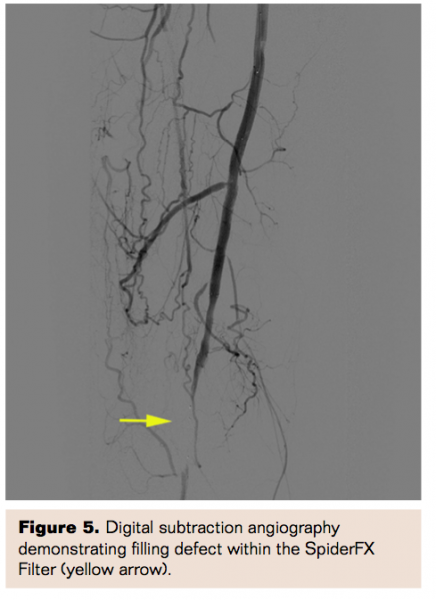

Angiography now demonstrated successful recanalization of the SFA with resolution of the thrombus, and brisk flow through the previously thrombosed segment. However, a prominent filling defect was noted within the filter of the SpiderFX (Figure 5). A culprit stenosis was identified at the distal edge of the lower Viabahn stent. This was treated by placing a Zilver PTX stent (Cook Medical) in an overlapping fashion with the previous stent. The SpiderFX was removed and upon examination was noted to have trapped thrombus, which was believed to be the cause of the filling defect noted above. Repeat angiography revealed a widely patent femoropopliteal segment, and preserved 3-vessel run-off with no signs of distal embolization (Figure 6).

The Trellis-6 catheter was removed, and angiography confirmed an excellent angiographic result, with return of stent patency and preservation of infrapopliteal flow. As in the prior case, an angiographic filling defect was noted in the SpiderFX filter.